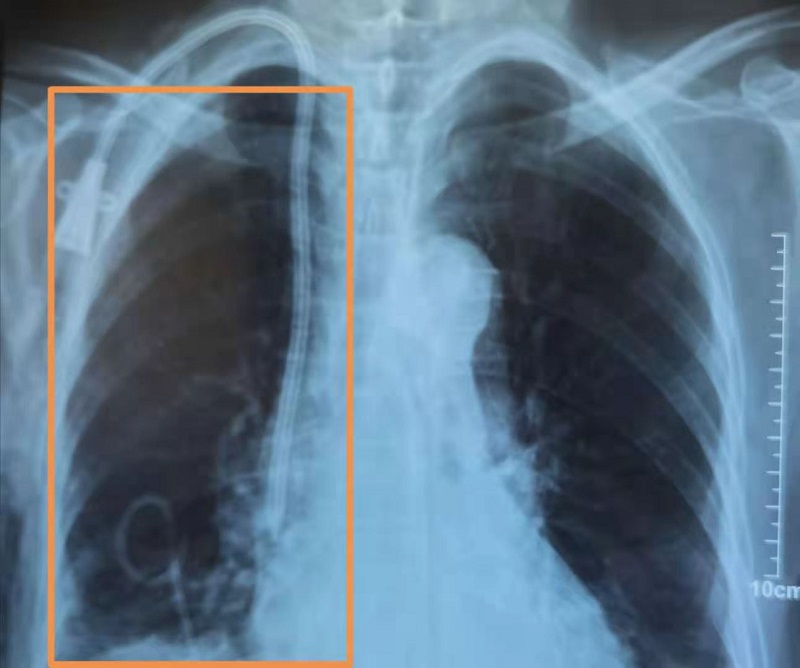

患者女性,68歲,患慢性腎衰竭、尿毒癥多年,1月26日入住我院腎病科進(jìn)行維持性血液透析治療。入院時(shí),胸悶、氣短、身體乏力,并伴有咳嗽、咳痰等癥狀,胸部CT檢查提示右側(cè)液氣胸,右肺肺不張(外壓型)。本著為病人全程負(fù)責(zé)的理念,腎病科及時(shí)邀請外科會診,外科建議立即請B超室配合行胸腔穿刺閉式引流術(shù),否則患者將會有生命危險(xiǎn)。隨后,腎病科和B超室協(xié)作,緊急為患者進(jìn)行了B超引導(dǎo)下穿刺引流,手術(shù)過程順利。

術(shù)后患者胸悶、氣短、乏力、咳嗽等癥狀明顯好轉(zhuǎn),1月31日復(fù)查胸片,氣胸明顯改善,右肺復(fù)張。2月1日上午拔除閉式引流管后,患者生命體征平穩(wěn),趨于好轉(zhuǎn)。